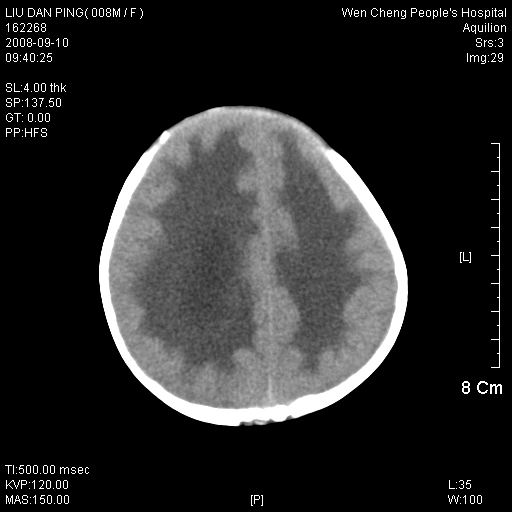

以下是引用卜一在2008-9-10 16:21:00的发言:[br]髓母细胞瘤伴梗阻性脑积水!支持![br]髓母细胞瘤特点:—般直径大于3.5cm,位于后颅凹中线之小脑蚓部。累及上蚓部的肿瘤延伸到小脑幕切迹之上,ct平扫肿瘤多呈均匀一致的高或等密度病灶,增强检查呈均匀一致的强化。病灶中有小坏死时,平扫亦可呈不均匀之混杂密度,注药后有增强。[br]

以下是引用zjzjr在2008-9-10 15:09:00的发言:[br]髓母细胞瘤伴梗阻性脑积水.